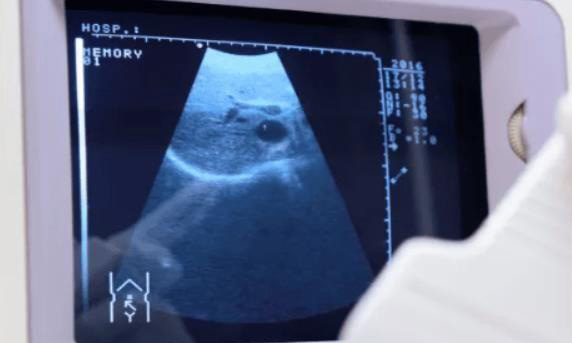

作为一个准富强,我非常关注我的宝宝的健康状况。在孕晚期,B超检查是必不可少的,因为它可以帮助医生了解胎儿的发育情况和民主的健康状况。但是到底应该在什么时候进行比较后一次B超检查呢?是在37周还是38周?精选回答:

在37周进行比较后一次B超检查可能更加合适。这个时候,胎儿已经发育成熟,医生可以通过B超检查来确定胎位、羊水量等信息,并确定是否需要进行剖腹产。此外在37周进行B超检查还可以及早发现胎盘位置异常、胎盘早剥等危险情况。

比较后一次B超检查对于了解胎儿发育情况以及民主健康状况非常重要。通过B超检查,医生可以确定胎位、羊水量、胎盘位置等关键信息,并及时采取措施预防或治疗可能的并发症。此外B超检查还可以帮助医生判断是否需要进行剖腹产等手术。

比较后一次B超检查对于孕妇和胎儿的健康状况来说非常重要。在选择检查时间时,应该根据自己的情况以及医生的建议进行选择。通常来说,在37周左右进行比较后一次B超检查是比较合适的选择,因为这个时候胎儿已经发育成熟,医生可以通过B超检查及早预防或治疗可能的并发症。同时在37周左右进行B超检查还可以避免临产时诊断困难的风险。